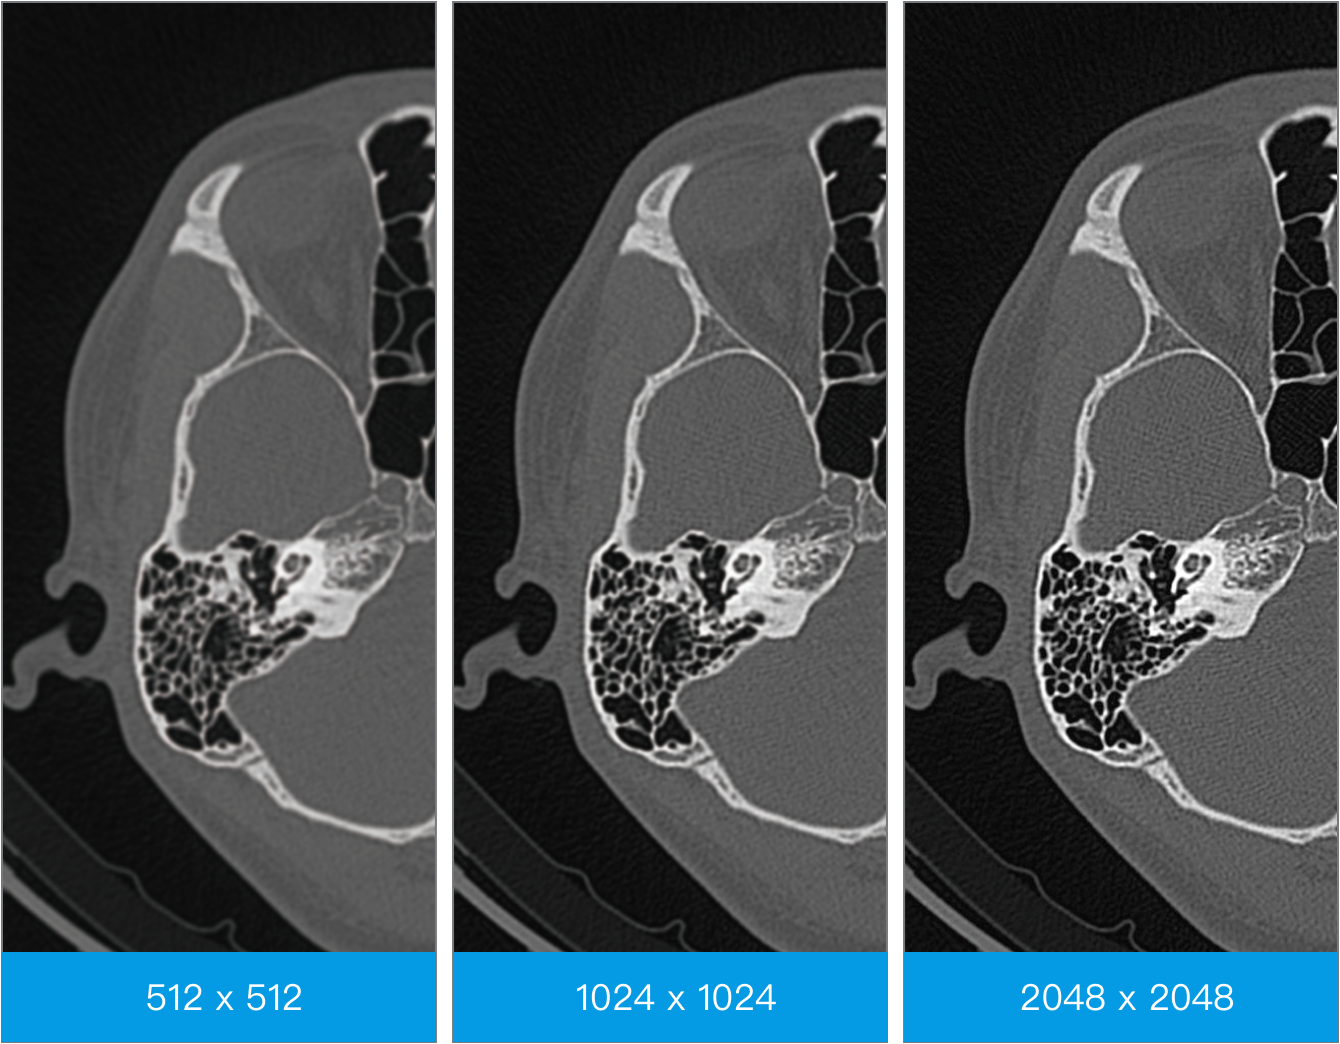

智能全域迭代iDream